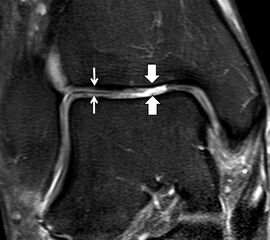

Jedoch findet man sich auch hier mit dem Problem der in den Standard-Projektionen schräg verlaufenden Syndesmose konfrontiert. Der oligofaszikuläre Aspekt der vorderen Syndesmose kann in der axialen Schnittebene eine zum Verwechseln ähnliche Morphologie wie eine Ruptur aufweisen (Abb. 15 b und c). Doppelangulierte Schnitte entlang der Achse (schräg koronar/schräg sagittal) lassen hingegen eine eindeutige Beurteilung der Bandstrukturen zu (Abb. 16) und verbessern die Syndesmosendiagnostik.

Bezogen auf die Transversalebene verläuft die Syndesmose ca. 30° schräg cranio-caudal anguliert (Abb. 15 a). Häufig lassen sich drei Hauptfaszikel differenzieren: das kürzeste superiore, das stärkste mittlere und das längste kaudale Faserbündel. Ein akzessorisches Bündel, das anteriore-inferiore, tibiofibulare Ligament (AITFL) oder auch Bassett-Ligament wird in 80-94% der Patienten nachgewiesen 8. Dies weist einen unmittelbaren Bezug zur anterolateralen Talusschulter auf (Abb. 17). In Kombination mit einer Außenbandinstabilität und konsekutivem, talarem Vorschub kann dieses zu einem Impingement an der anterolateralen Taluskante führen mit nachfolgender chondraler oder osteochondraler Läsion.

b. T2 fs axial. Infraktion des hinteren Volkmann‘schen Dreiecks (schmale, weiße Pfeile). Hier inserierende, intakte, hintere Syndesmose (breite, weiße Pfeile).

Da also die hintere Syndesmose an der posterioren Tibia inseriert, entspricht eine Fraktur oder Infraktion des hinteren Volkmann`schen Dreiecks funktionell einem knöchernen Ausriss des Ligamentum tibiofibulare posterius (Abb. 18 a und b). Aufgrund der Koinzidenz von Syndesmosenläsionen mit Innenbandverletzungen ist bei der Beurteilung gesondert auf solche zu achten.